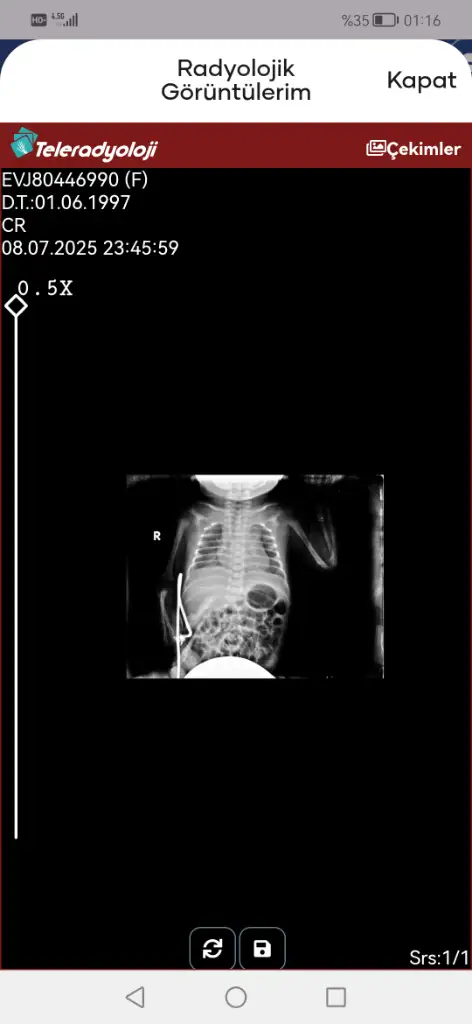

Eklentiler

• Screenshot_20250709_142908_tr.gov.saglik.enabiz.webp

Screenshot_20250709_142908_tr.gov.saglik.enabiz.webp

16,8 KB · Görüntüleme: 19

• Screenshot_20250709_011620_tr.gov.saglik.enabiz.webp

Screenshot_20250709_011620_tr.gov.saglik.enabiz.webp

14,3 KB · Görüntüleme: 27

Veriyorlar yeni yeni. 2 gündür entübe değil ama bugün nasıl şuan bilemiyorum kan değerleri bu şekilde

Evet entübasyon hortumu görünmüyor iki hortum olmalıydı ağzında. Entübeden ayrılması da iyi bir şey süt de azıcık gaz yapmış hatta bebişe. Süt aldıkça bu değerler toparlanır. Kan gazına göre bebeğiniz solunumu tölere edebiliyor diyebiliriz bunlar güzel haberler